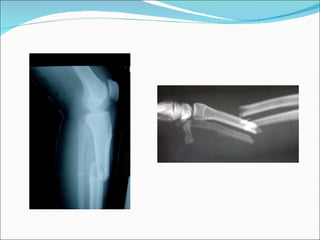

Causes Fracture of a long bone (Supracondylar humerus, forearm, hand,tibia and foot)

Causes Fracture ofa long bone (Supracondylar humerus, forearm, hand,tibia and foot)